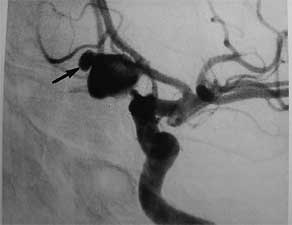

Obraz tętniaka olbrzymiego - tętniak olbrzymi

/ Fot. (tętniak olbrzymi)